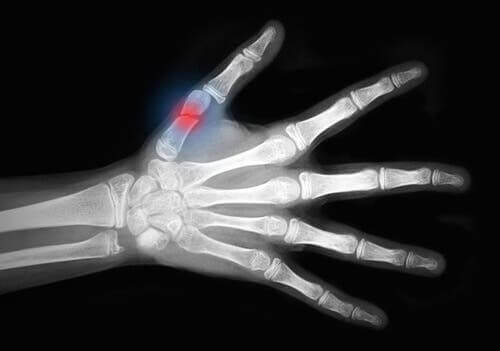

في المجال الطبي، تعتبر إصابات اللحب والتي تندرج ضمن إصابات الأنسجة الرخوة للجلد على مساحات واسعة والتي تتسبب في كشف أنسجة العظام. وفي الغالب ما تقع هذه الإصابات بشكل رئيسي في الأطراف.

- إعادة الزرع. ونقصد هنا إعادة تجميع أجزاء الجسم التي تم بترها. على سبيل المثال، أصابع اليد.